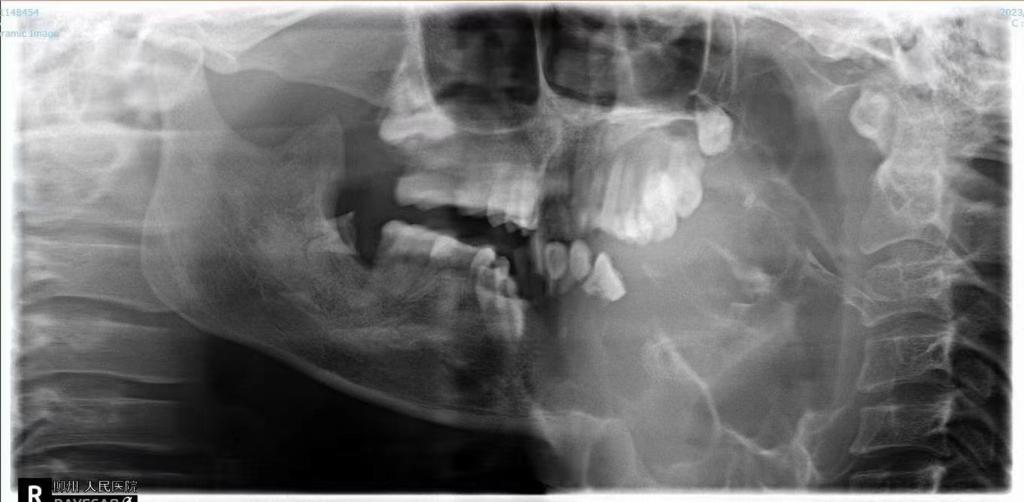

無奈之下,近日,劉女士在家人的陪同下來到了柳州市人民醫院口腔科就診。接診的副主任醫師劉彥杰看到患者情況后也有些吃驚,這是他從醫多年見過的最大的下頜骨腫瘤。經檢查發現,腫瘤已經完全侵犯患者左邊下頜骨,口腔內還有一大塊腫瘤暴露,左下牙已經完全被腫瘤侵犯消失,腫瘤很容易出血,上頜骨也被腫瘤壓迫變形。好在腫瘤表面皮膚還比較完整,可以用來做術后口腔缺損的修復。

患者入院后活檢結果為成釉細胞瘤,成釉細胞瘤是常見的牙源性上皮性良性腫瘤之一,又稱造釉細胞瘤,該病初期發展緩慢,無自覺癥狀。逐漸發展可使頜骨膨大,造成畸形,左右面部不對稱。腫瘤侵犯牙槽骨時,會使牙松動、移位或脫落;腫瘤繼續增大,會使頜骨外骨板變薄,甚至吸收,這時腫瘤可以入侵軟組織;當腫瘤壓迫下牙槽神經,患側下唇及頰部可能感覺麻木不適;如腫瘤發展很大,骨質破壞較多,會發生病理性骨折。

口腔科立即在科內開展了病例討論,考慮到患者下頜腫塊異常巨大,再結合其經濟狀況,首要治療就是先切除腫瘤,二期手術再進行下頜骨的修復重建。該手術的難點主要體現在兩方面:第一是精準切除腫瘤,需要腫瘤切除醫生團隊積累沉淀豐富手術經驗,才能把腫瘤完整切除;第二是對缺損部位進行外形、功能的精確修復,這一步相對更難、更復雜。